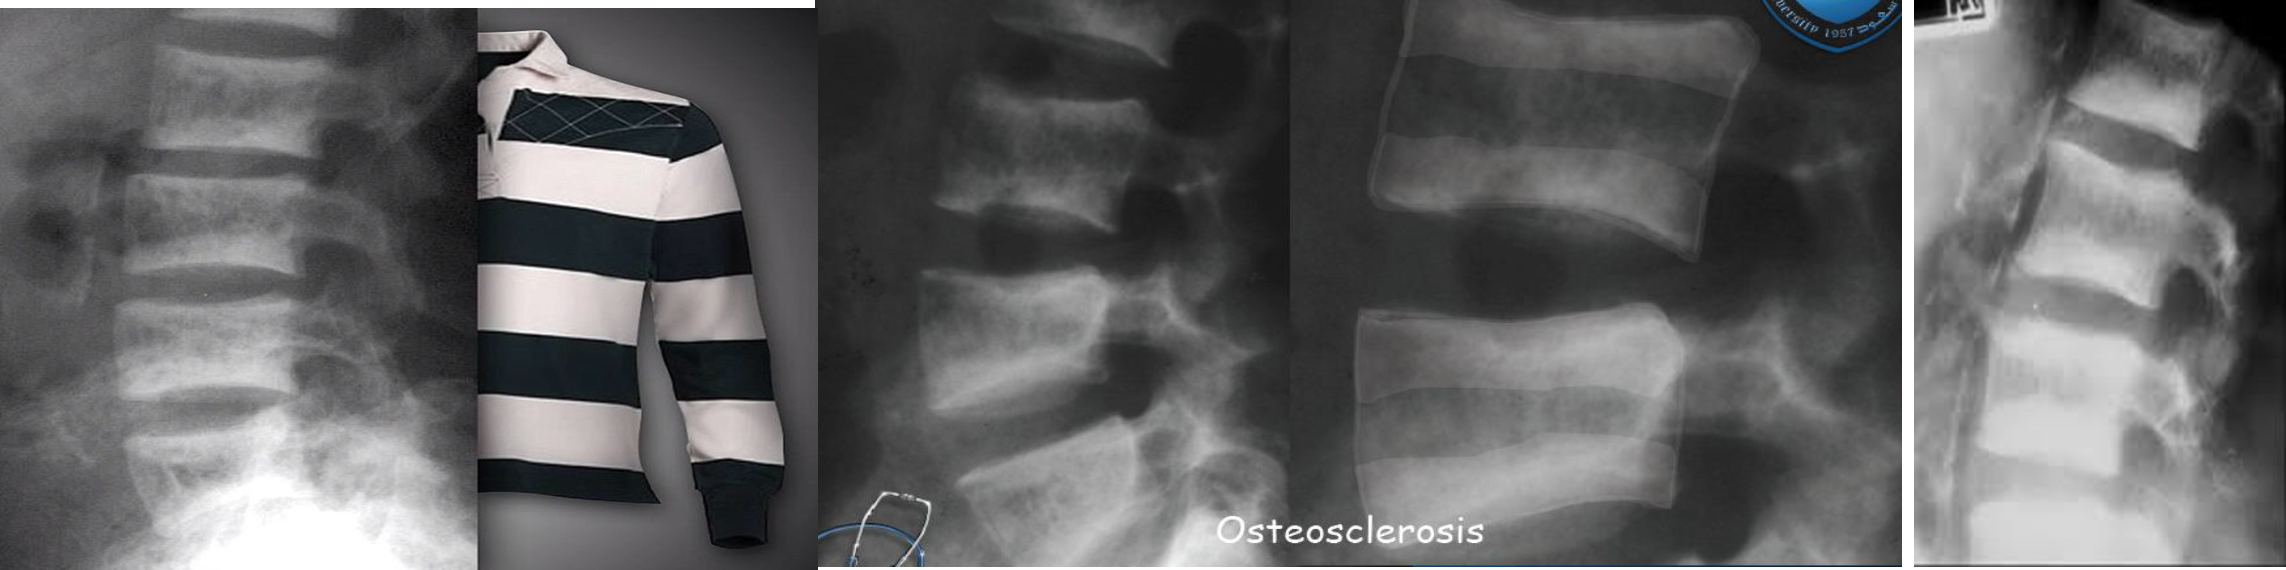

Ruger Jersey spine : secondary hyperparathyroidism z

Occurs due to renal failure/renal osteodystrophy prominent endplate densities at multiple contiguous vertebral levels to produce an alternating sclerotic-lucent-sclerotic appearance

On x-ray white margins with lucent central and vertical trabeculae, which is called( Ruger Jersey spine) these, (changes are due to renal dystrophy.

- Decreased bone density of the central portions (black area)

- Sclerotic vertebral end plates

(renal osteodystrophy). There are sclerotic bands running across the upper and lower ends of the vertebral bodies of the lumbar spine (arrows).